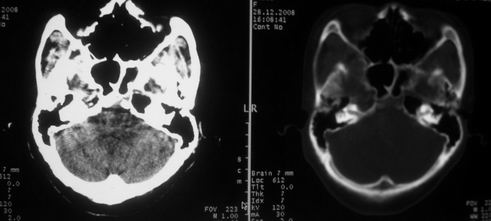

女,72岁,头晕。额骨有无问题。

额骨呈磨玻璃状增厚,考虑骨纤。

额骨呈磨玻璃状增厚,考虑骨纤

骨纤维组织异常增殖症又名纤维性骨炎,是一种以骨纤维变性为特点的骨胳系统疾病,是否为一真性肿瘤尚无定论。该病好友于儿童及青年,女性较多见,60%发生于20岁以前,偶见于婴儿和70岁以上老年人。男女发病为1∶2。80%以上表现为病骨区畸形肿胀;建议祥问病史,时间?